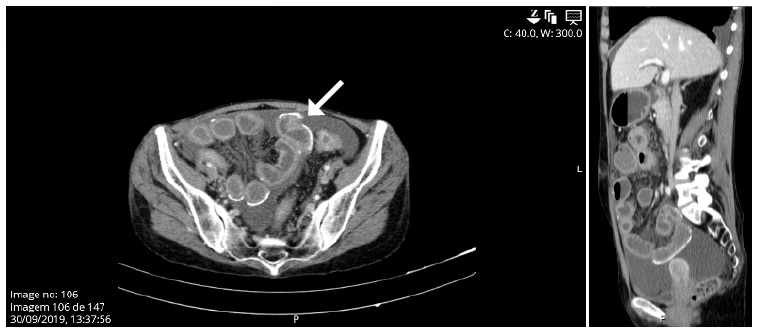

After 47 days of hospitalization, exploratory laparoscopy was then decided. Intraoperative laparoscopic findings showed exuberant peritoneal adhesions, fibrin in all quadrants, frozen loops, and multiple abdominal collections with citrine fluid but without pus. The patient was submitted to extensive enterolysis and partial removal of fibrin plaques (Fig. 2).

Figure 2 Findings during enterolysis. Multiple intra-abdominal adhesions of bowel loops by cobweb-like sclerotic membranes.